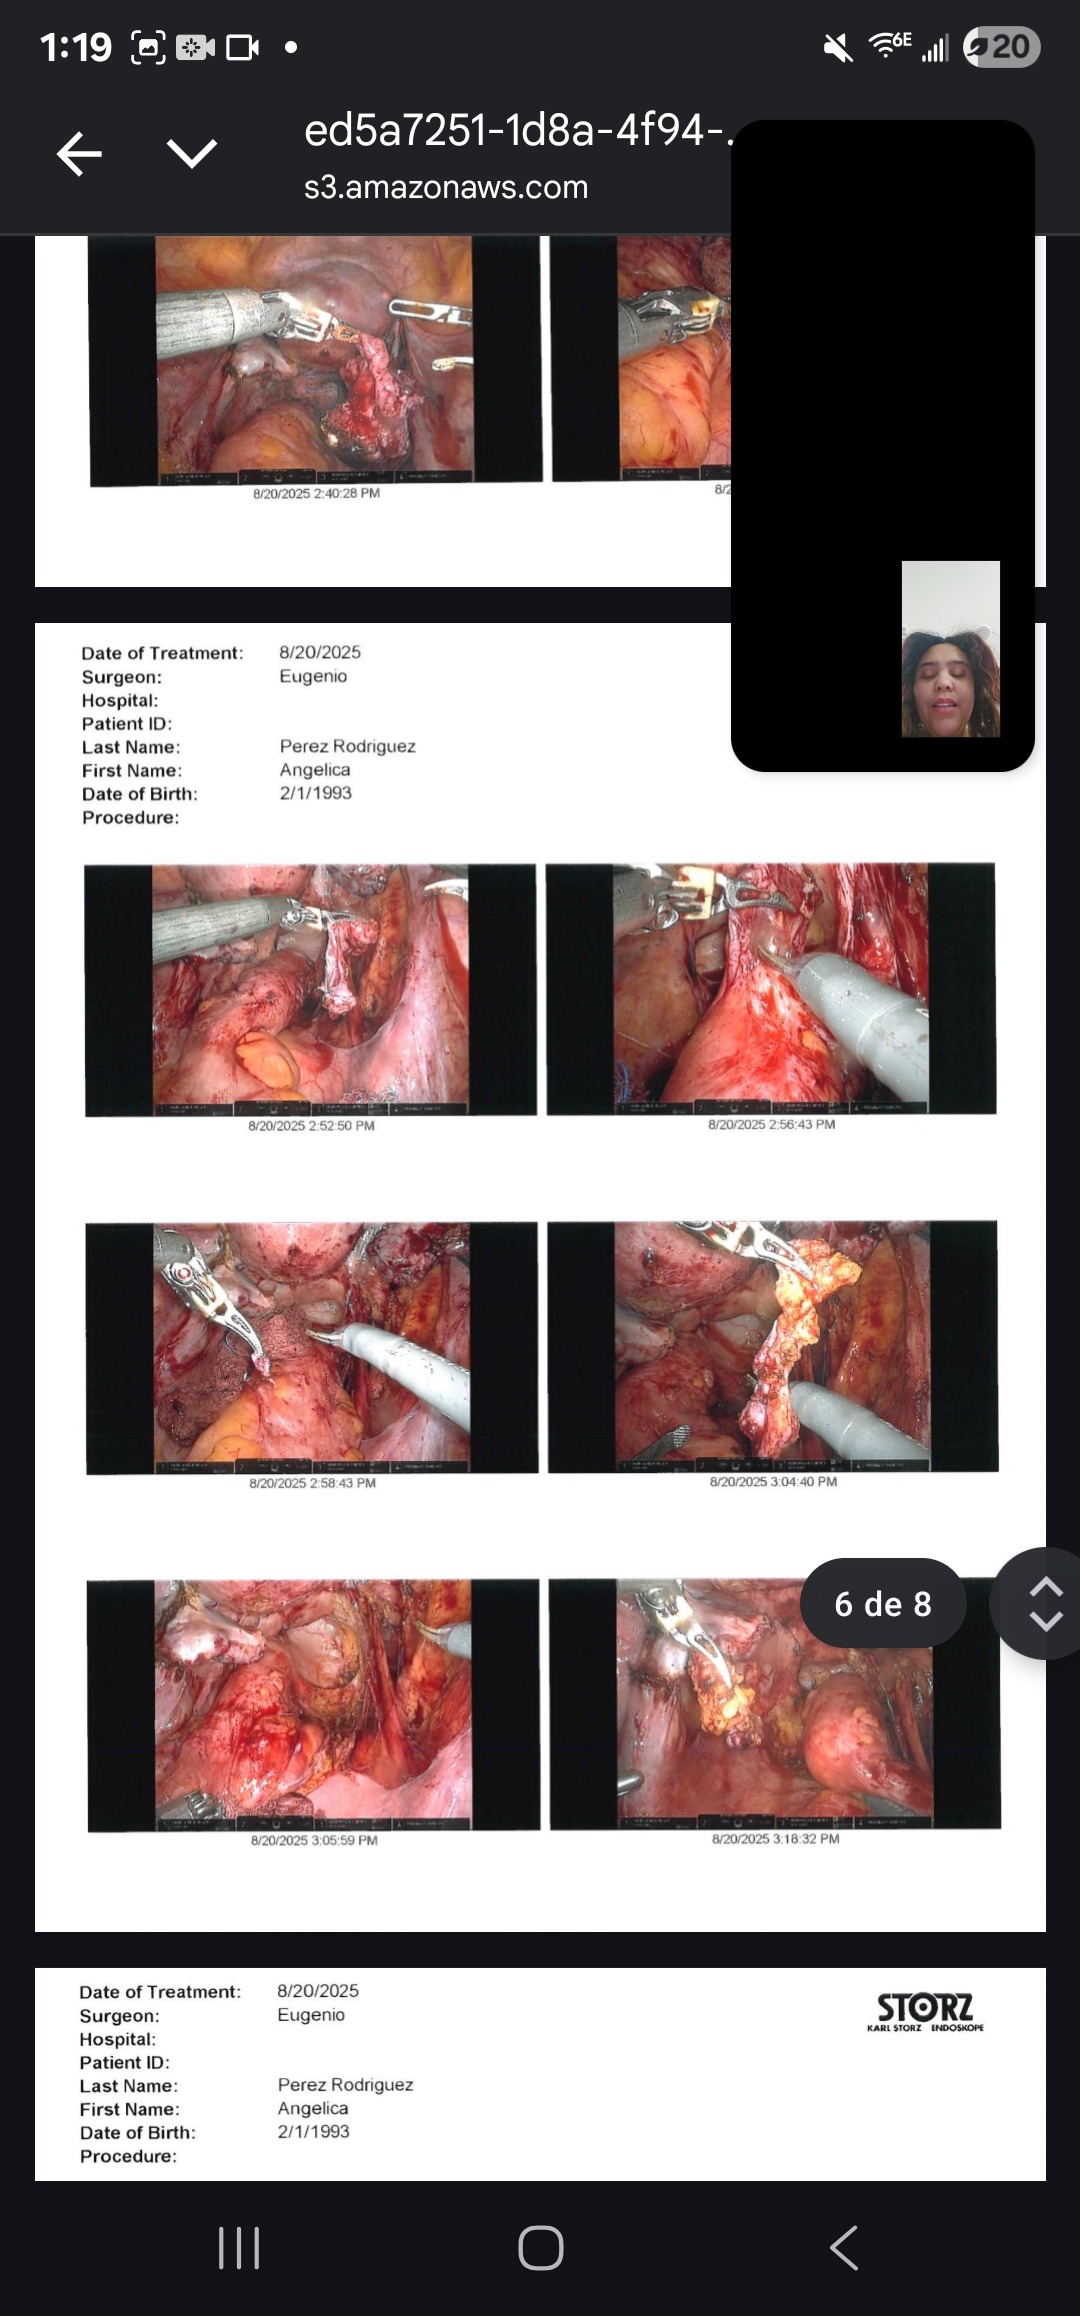

My name is Angelica, and I am fighting Stage 4 deep infiltrative endometriosis. Since 2022, I have gone through 5 surgeries — 3 of them just in the past year. Each operation has been an attempt to ease the pain and give me a chance at a normal life, but the fight is far from over.